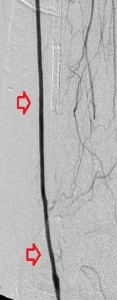

Key to images:

Top panel: Pre-intervention run-off angiogram of the left lower extremity showing, from left to right, irregular left common femoral artery (LCFA) arrowed on the 1st image, absent left superfical femoral artery (LSFA) or any bypass conduit on the 2nd image, sketchy descending collaterals from the left deep femoral (LDFA) that reconstitute a faint shadow of the left popliteal artery, arrowed on the 3rd image. The last 2 images faintly show three-vessel run-off below the left knee. The anterior tibial artery is most opacified, followed by the posterior tibial artery; the peroneal artery peeps through the upper edge of the last image. Note how weakly visible these vessels are due to the poor inflow from above.